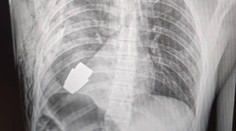

Zmiznú bez ďalšej operácie. Lekári pri zlomeninách čoraz viac používajú takzvané neviditeľné skrutky, ktoré sú podobné ľudskej kosti.

Pacient nemusí absolvovať ich odstránenie, pretože sa vstrebú. Na nové trendy v chirurgii sa školili poprední chirurgovia a ortopédi.

Tradičné kovové implantáty postupne nahrádzajú neviditeľné biovstrebateľné. So skrutkami sa u nás zoznamuje čoraz viac odborníkov.

Ide o materiál, ktorý sa po 24 hodinách v ľudskom tele rozšíri a skráti. Ostáva taký pevný ako kosť.

„Po ôsmich týždňoch začne degradovať a následne po dvoch rokoch je kompletne zmetabolizovaný v ľudskom tele,“ vysvetlil Martin Haas zo Pharma Care Slovakia.

​To znamená, že pacient ide na operáciu len raz.

Na Slovensku sa pri zlomeninách použilo už viac ako 600 takýchto implantátov. Preplácajú ich aj zdravotné poisťovne.